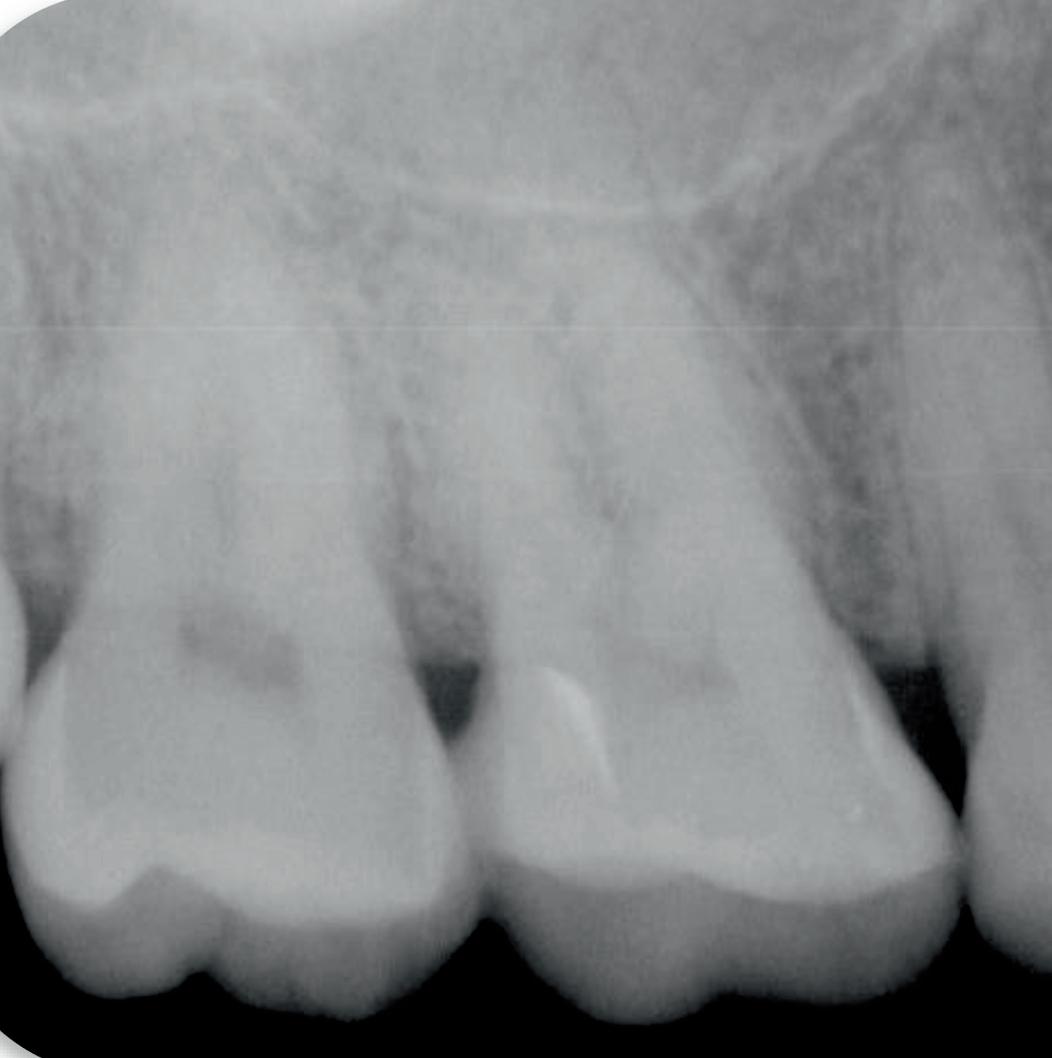

Tri Auto ZX2+